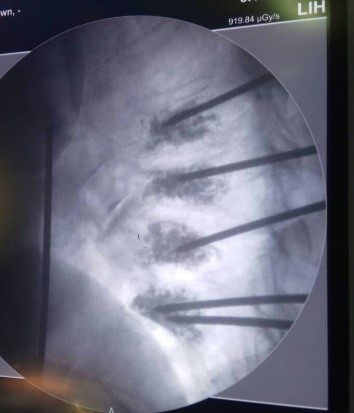

- Паравертебральные и пресакральные блокады при выраженных формах болевого синдрома, в том числе под контролем современной операционной рентген-установки;

- Вертебропластика, кифопластика современными системами (Италия, США, Франция) при гемангиомах, патологических переломах на фоне остеопороза, спондилопатиях;